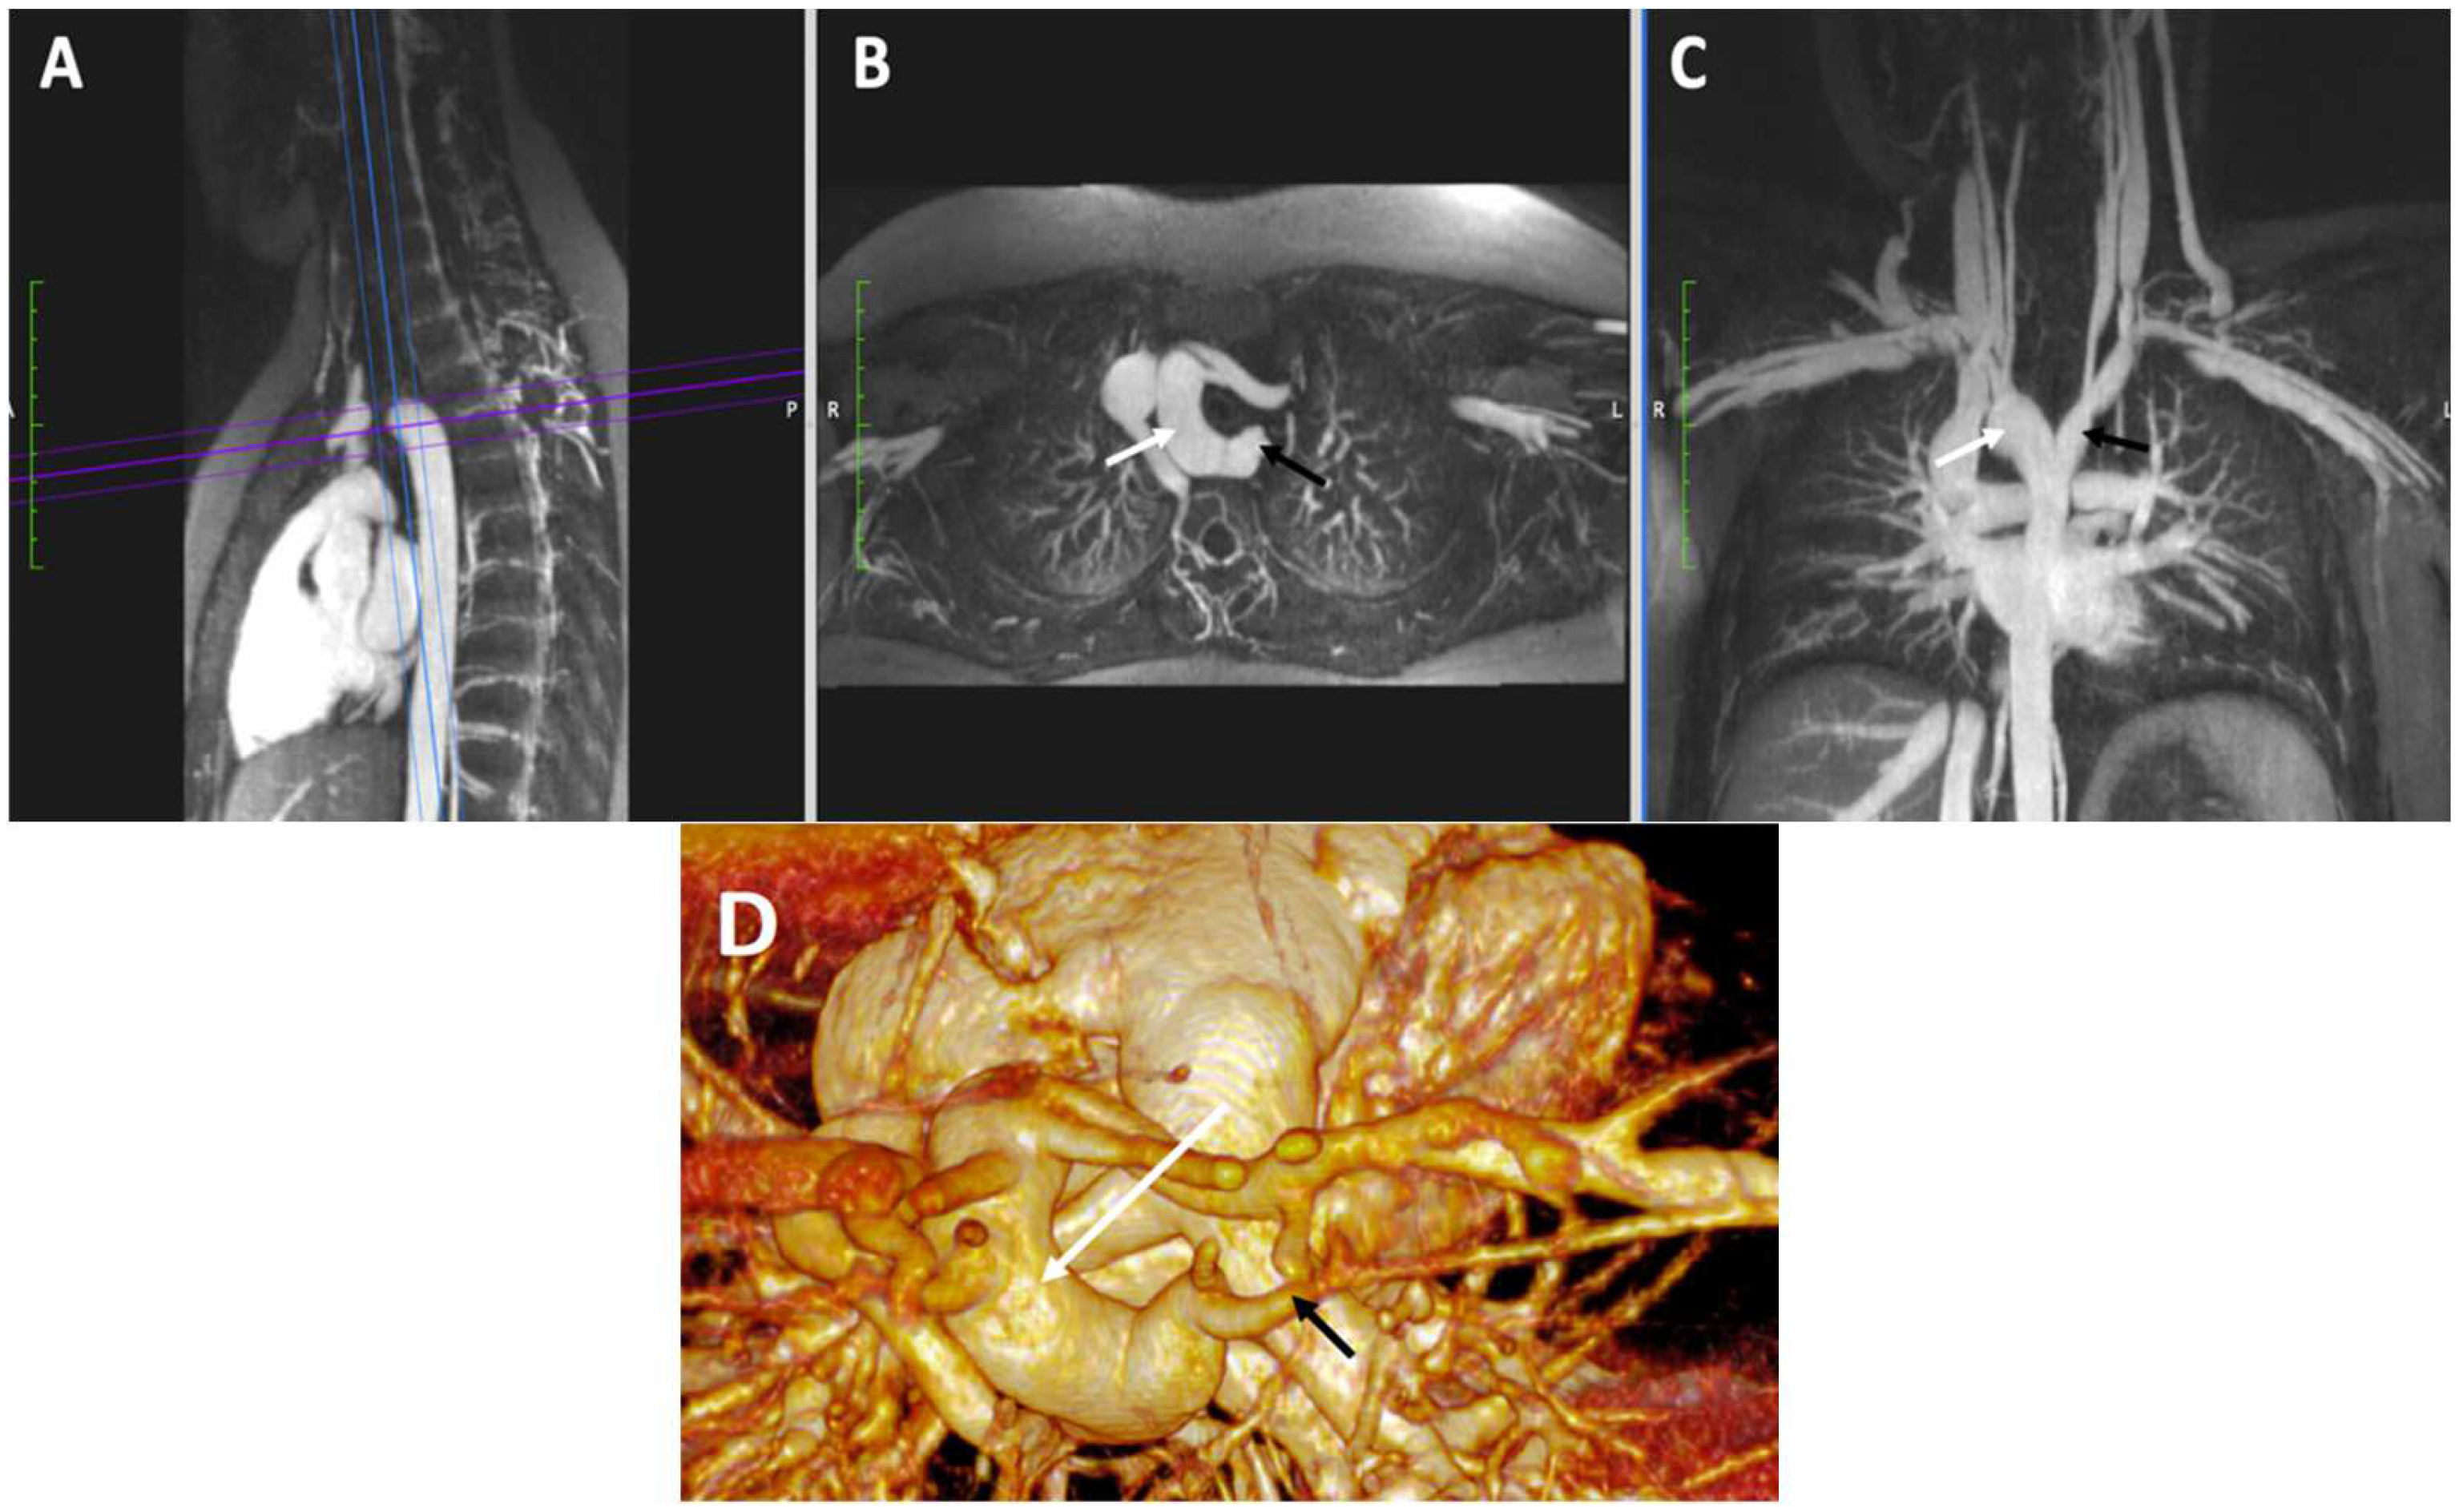

4.3.3. Vascular Ring

- Bakker, D.A.; Berger, R.M.; Witsenburg, M.; Bogers, A.J. Vascular rings: A rare cause of common respiratory symptoms. Acta Paediatr. 1999, 88, 947–952. [Google Scholar] [CrossRef] [PubMed]